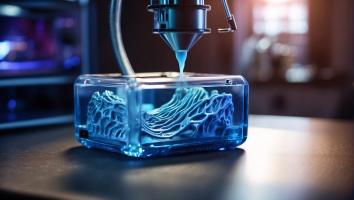

RÉPARATION OSSEUSE : Générer des fémurs en 3D